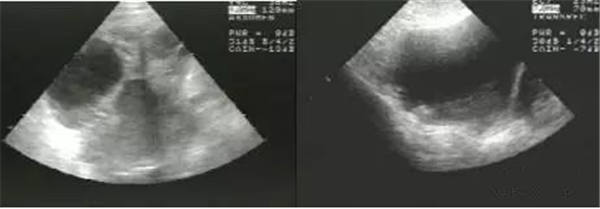

上圖:

右室壁運動幅度減低

正常情況下,右室前壁運動幅度應>5 mm,右室游離壁運動幅度會>8 mm,但對肺栓塞(PTE)患者,右室壁基底部至游離部運動幅度減低,甚至消失。

幅度降低可視但并非一個量化的標準,因此在把握和判斷上存在疑議,這里呢就為大家分享一點觀察的要點,同樣看圖說話:

正常聲像圖

PTE患者右室壁運動明顯減低